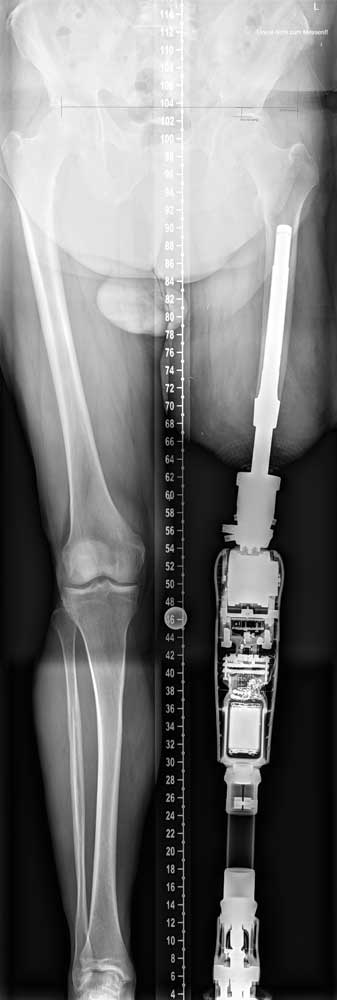

Statischer Prothesenaufbau und Besonderheit des Brückenzylinders

Die Grundprinzipien des Prothesenaufbaus unterscheiden sich beim TOPS nicht von schaftgeführten Prothesen; die Passteile werden entsprechend den Herstellerinformationen aufgebaut. Die Besonderheit stellt die unmittelbare knöcherne Verbindung der Prothese dar. Aus diesem Grund sollten dem Orthopädietechniker beidseitige Ganzbeinaufnahmen zur Verfügung stehen. Hierdurch kann eine exakte Position der Längs- und Drehachsen der Knie- und Fußpassteile erreicht werden. Für die unmittelbare Verbindung der Exoprothese mit dem Brückenzylinder ist aus statischen Gründen ein Rückverlagerungsadapter notwendig. Die Größe des Modules ergibt sich aus den Anforderungen der Passteile sowie einer ggf. bestehenden Hüftbeugekontraktur. Insbesondere Letztere ändert sich innerhalb der ersten Wochen aber deutlich, sodass Anpassungen der Rückverlagerungsadapter notwendig sein können. Für den Fall ungewollter sehr hohe

Torsionsmomente von der Prothese auf den Knochen, welche zur Periimplantierenbrüchen führen würden, befindet sich innerhalb des Brückenzylinder eine Sollbruchstelle (Abb. 11). Diese wird durch Torsionssperrkörperelemente (50–130 Nm) eingestellt und muss an die aktuelle Belastung und Gewichtssituation angepasst sein. Somit kommt es zur gewollten Aufnahme der Torsionsspannung in den Brückenzylinder mit kontrolliertem Brechen der Sperrstifte und ein Knochenbruch kann vermieden werden.